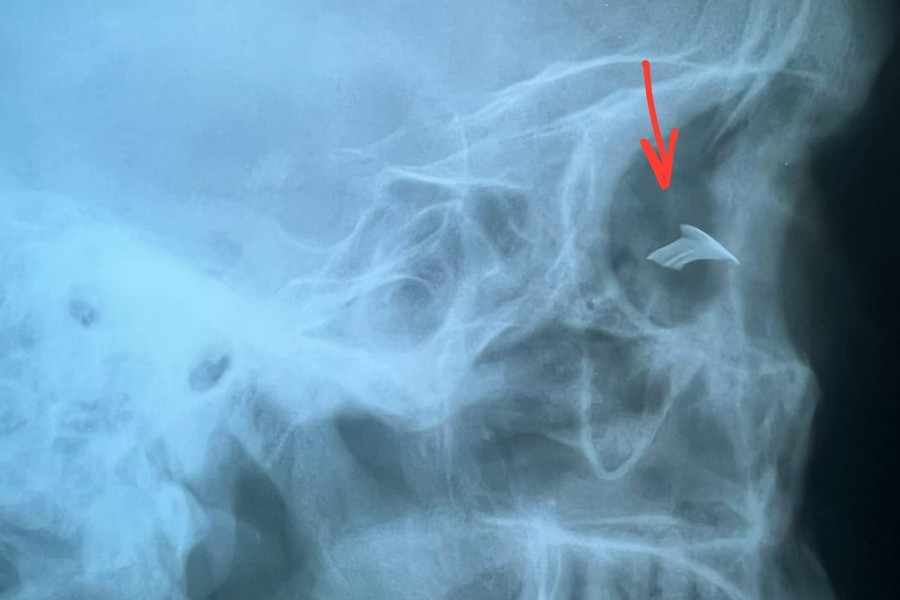

В кабинет неотложной помощи обратился пациент с травмой глаза. Со слов пациента он работал со строительным пистолетом без защитной маски. В какой-то момент заметил, что кусочек металла отскочил и ударил по лицу.   При осмотре и рентгенологическом исследовании было выявлен осколок металлической плотности в правой глазнице.

« Травмы глаз порой очень непредсказуемы. Осколок был удален у экватора глазного яблока. Операция прошла успешно. Прогноз благоприятный. Пациент видит 9 строчек (90% зрения). В этом случае закончилось всё хорошо. Пациент выписан на дальнейшее консервативное лечение по месту жительства », - рассказывает заведующий вторым офтальмологическим отделением, врач-офтальмолог  Татьяна Николаева .